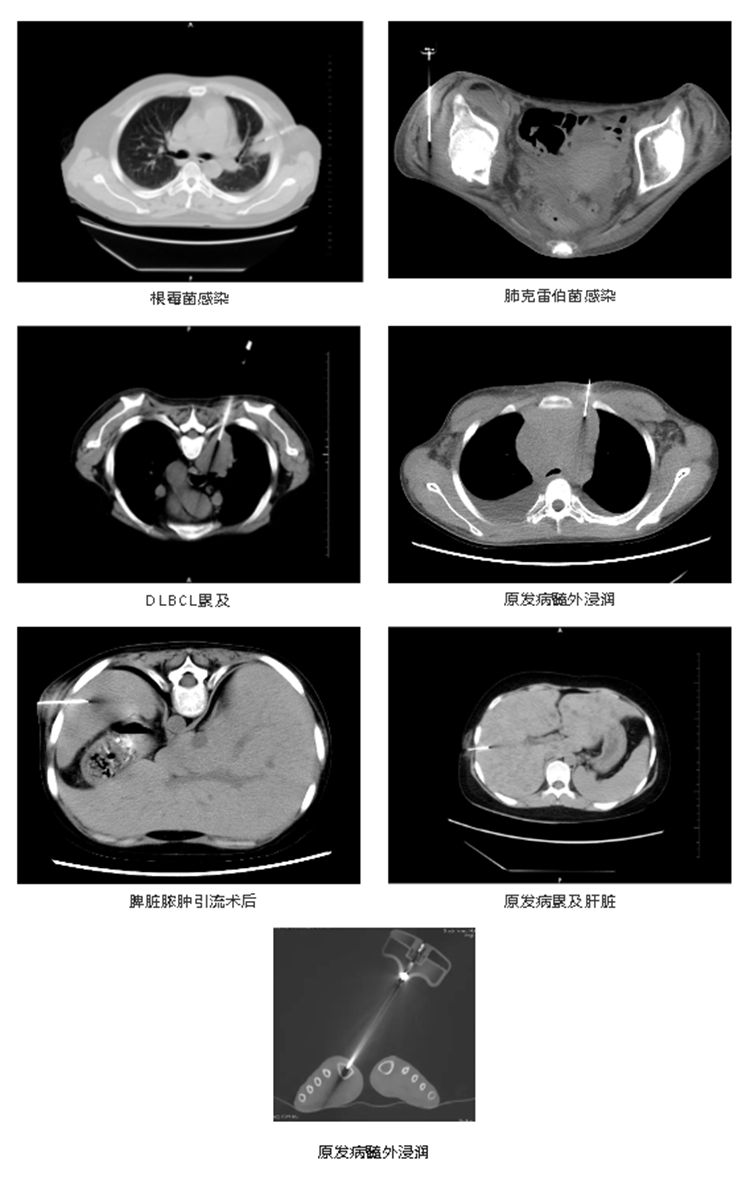

實(shí)際病例展示

感染性病變(明確病原學(xué)性質(zhì))

血液病髓外病變性質(zhì)確定

治療(局部注藥、膿腫引流)